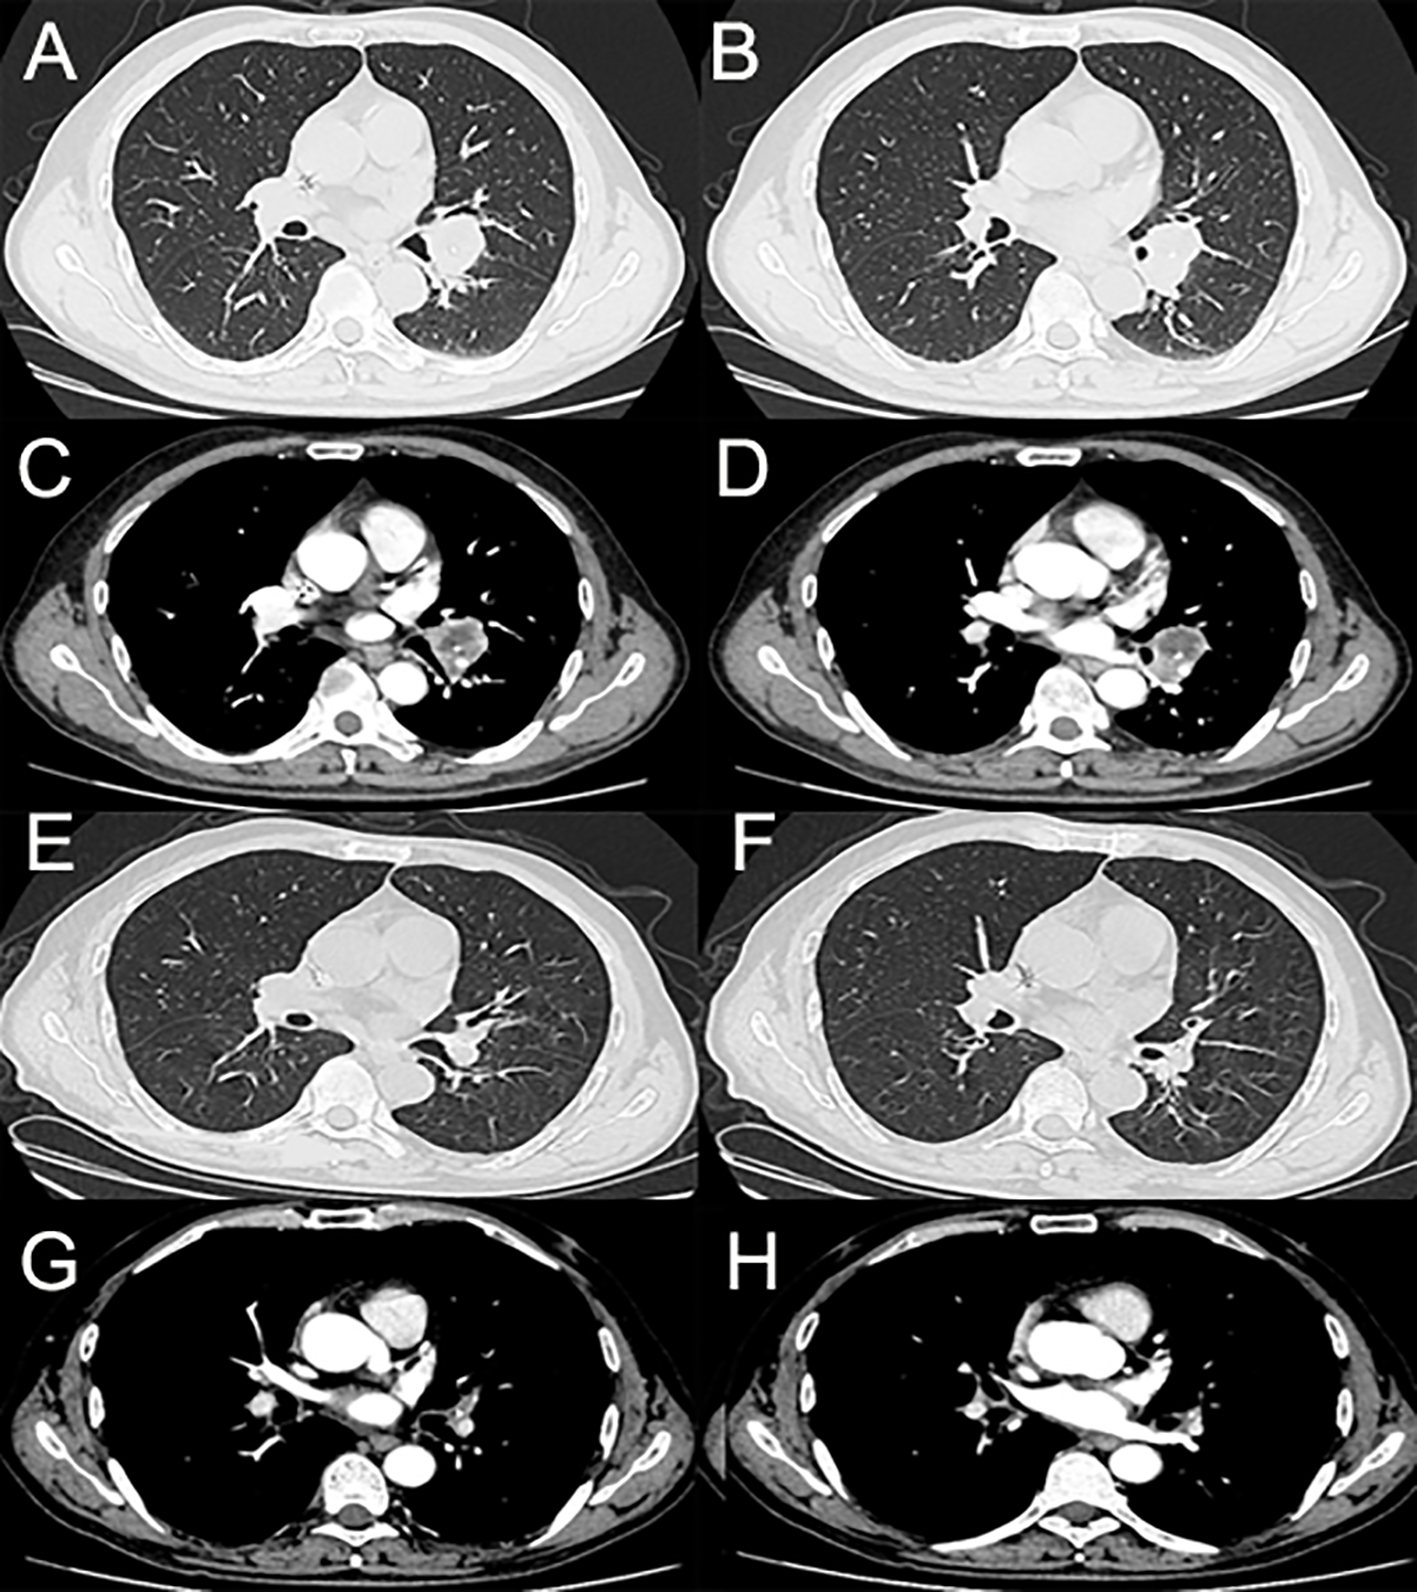

A 59-year-old man was admitted to our hospital for the treatment of centrally located squamous cell-lung carcinoma and pulmonary tuberculosis. The computed tomography (CT) scans showed that the malignant lesion, located between the left upper and lower lobes, had invaded the left pulmonary artery (Figure 1). Pathological and etiological findings revealed a combined diagnosis of squamous cell-lung cancer (T3N0M0) and pulmonary tuberculosis. Anti-tuberculosis therapy, which including Isoniazid (300 mg per day), Rifampicin (450 mg per day), Ethambutol (750 mg per day), and Pyrazinamide (1250 mg per day), without any adverse events, was administered to cure the pulmonary tuberculosis. Neoadjuvant therapy, including sintilimab and conventional chemotherapy, was administered to achieve a complete response (CR) or partial response (PR). After three cycles of neoadjuvant therapy, the patient underwent video-assisted thoracoscopic surgery (VATS) left lower lobectomy, because the malignant lesion had shrunk and the left pulmonary artery had been isolated from the tumor. No cutaneous toxicity was observed during the first three cycles of neoadjuvant therapy. According to the post-operative pathologic results, the neoadjuvant therapy resulted in a PR. Therefore, the sintilimab and conventional therapy were continued as post-operative adjuvant therapy.

Figure 1

(A–D) The enhanced computed tomography (enhanced-CT) scans of the tumor before neoadjuvant therapy. (E–H) The enhanced-CT scans of the tumor after three cycles of neoadjuvant therapy.